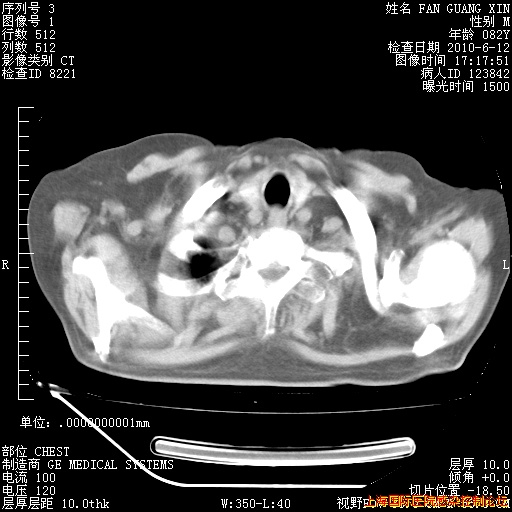

今天复查CT

今天CT

整整相隔30天的肺部CT好像有所好转啊。甲强龙减量第3天,需要观察体温。

海管,自昨日你和我通完话后,不知您岳父消化道症状有无缓解?体温怎样?阅读7.12日胸部ct,个人认为目前激素治疗是有效的,甲强龙减量是适宜的。因在抗痨治疗,需密切观察肝功、肾功能和血常规。不过,老年、长期住院和大量使用激素,很担心菌群失调发生